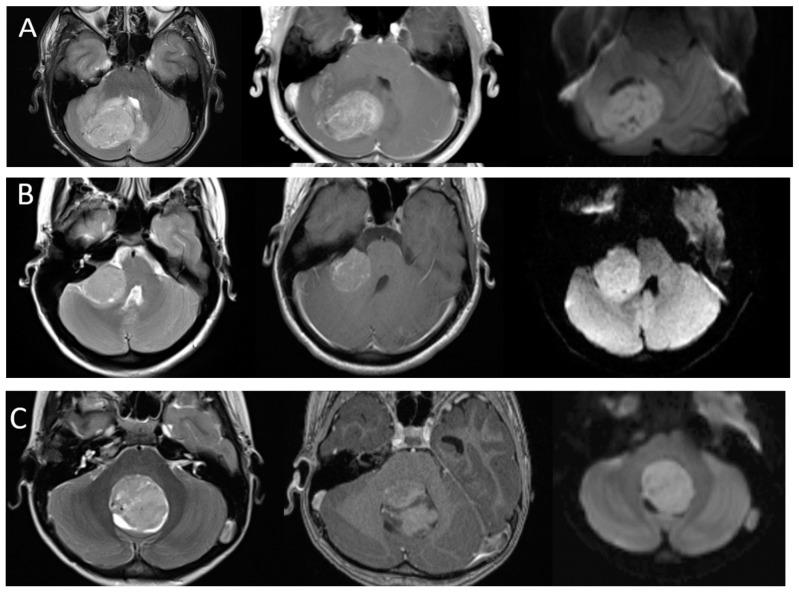

Primary brain tumors are the most common solid neoplasms in children and a leading cause of mortality in this population. MRI plays a central role in the diagnosis, characterization, treatment planning, and disease surveillance of intracranial tumors. The purpose of this review is to provide an overview of imaging methodology, including conventional and advanced MRI techniques, and illustrate the MRI appearances of common pediatric brain tumors.

原发性脑肿瘤是儿童中最常见的实体肿瘤,也是该人群死亡的主要原因。磁共振成像(MRI)在颅内肿瘤的诊断、特征描述、治疗规划和疾病监测中起着核心作用。本综述的目的是概述成像方法,包括传统和先进的MRI技术,并阐述常见儿童脑肿瘤的MRI表现。